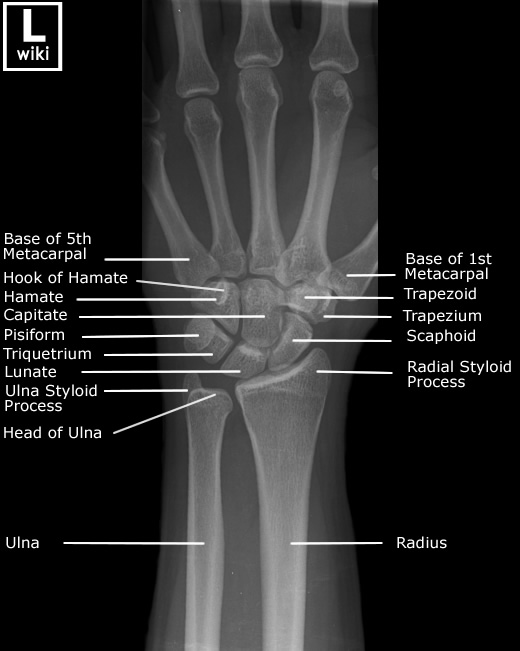

Wrist Radiographic Anatomy

| AP/PA View | Oblique View |

![]() |